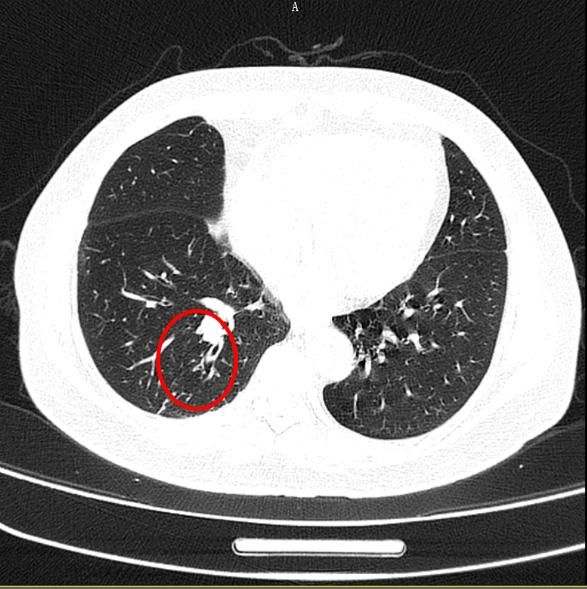

北京大学深圳医院呼吸内科徐平主任医师用气管镜为杨红(化名)取出肉芽肿和异物后,之前杨红肺部的白色肿块影像消失(见红色圈内部分)。杨红历时一年多的咳嗽终于治愈。

这个小小的辣椒尖,位于杨红右肺下叶后基底段,因为长期存在,还导致了支气管扩张及周围炎症(肉芽肿)。直到肉芽肿,以及被肉芽肿包裹的辣椒尖被取出后,杨红的咳嗽终于痊愈了。这令她非常高兴。